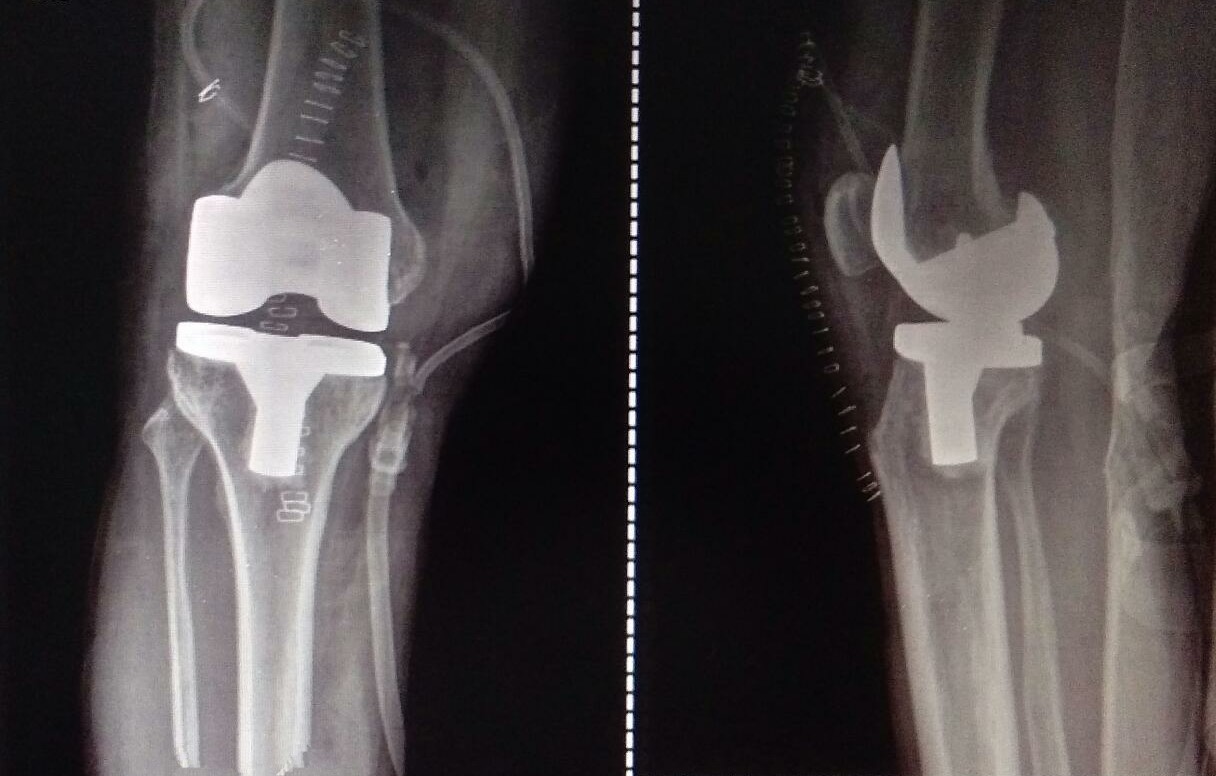

Knee and Hip Replacement